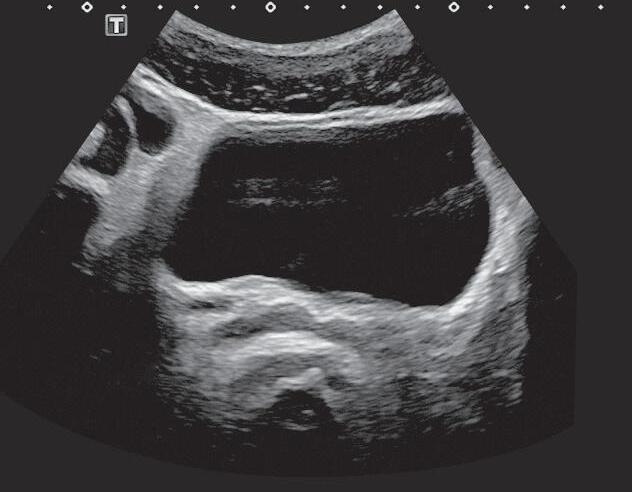

Vesículas seminais simétricas e com espessura e dimensões normais.

Fig. 1-9. Vesículas seminais.